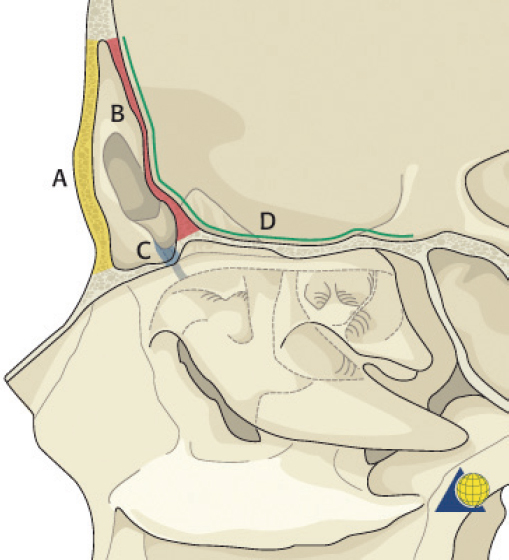

The nasofrontal recess is the sole outflow tract for the frontal sinus. The distance from the frontal sinus to the hiatus semilunaris is usually very short and is therefore most accurately described as a “recess” rather than a true duct. Each ostium is 1–3 mm in diameter and located on the posterior, inferior aspect of the sinus floor. The ostium lies anterior to the anterior ethmoid air cells, medial to the orbit, lateral to the intersinus septum, and posterior to the frontal bone. The true ostium represents the narrowest point of an hourglass configuration, with the frontal sinus infundibulum above and the nasofrontal recess below ( Fig. 63.3 ). 2 The vascular supply to the frontal sinus is from the supraorbital and supratrochlear arteries via the internal carotid system. Venous drainage occurs through three pathways: the facial vein, the ophthalmic vein (to the cavernous sinus), and the foramina of Breschet (to the subarachnoid space). 6 The ophthalmic branch of the trigeminal nerve provides sensory innervation to the frontal sinus.